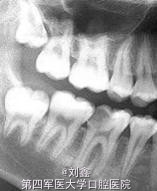

男,16岁,46因牙龈息肉就诊。

46牙牙龈息肉

局麻下牙龈息肉切除及开髓去腐,后牙根管治疗后纤维桩+树脂充填

采用纤维桩+树脂充填还是桩冠修复我也纠结过,其实根据影像、牙齿的生长发育和实际情况,我个人认为这样的病例做桩冠修复也是合情合理。但患者的家长考虑小孩子尚小处于生长发育期倾向前者,何况成年后也可直接行冠修复!